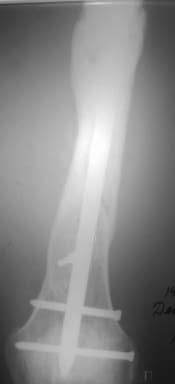

Александр Николаевич, к сожалению больной не является на контрольные осмотры. Я последний раз видел больного, когда прошло 7 месяцев после операции БОС. У него все хорошо. Каких либо жалоб и ограничений в нагрузке нет. Высылаю снимки до операции и последние снимки.